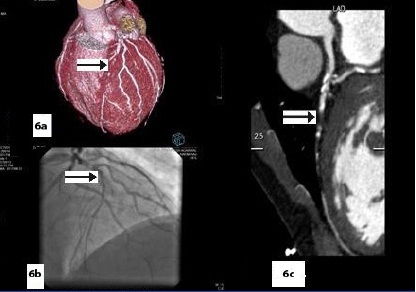

Five patients (12.5 %) had normal angiograms [Table/Fig-2,2b,3,3b], six (15%) had non-significant disease [Table/Fig-4,4b,5a,5b] and 29 patients (72.5%, 26 male & 3 female) had significant disease [Table/Fig-6a,6b],[7a,7band8] on CT coronary angiography, which was also proved on invasive angiography [Table/Fig-9]. The incidence of significant coronary detected was highest in age group of 41-60 years [Table/Fig-10].

Curved reformatted image shows non- calcific plaque near origin of OM1 causing significant stenosis,

Catheter angiography image showing significant stenosis of OM1 at origin Significant disease in the absence of calcification